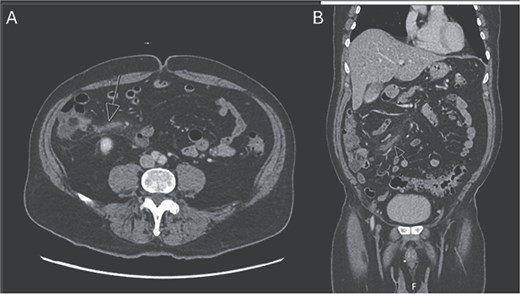

The patient was admitted to the surgery service for resuscitation and close monitoring. Given his prior thrombotic event, the patient was started on a continuous heparin infusion, anti-Xa goal 0.3–0.7. The patient received 2 L of intravenous fluids as well as a continuous fluid infusion of lactated ringers at 100 cc/hr. The surgery team performed serial abdominal exams which remained stable. Additionally, he was started on prophylactic ceftriaxone and metronidazole. A CTA abdomen and pelvis was subsequently performed, which revealed occlusion of the ileocolic vein with perivenous inflammatory change, consistent with mesenteric thrombophlebitis (Fig. 2). The celiac trunk, superior mesenteric artery, renal arteries and inferior mesenteric artery were all patent. Venous phase imaging showed patent portal vein and patent main superior mesenteric vein. On hospital day (HD) 1, the patient’s lactic acidosis cleared. A GI PCR was obtained which was positive for enteropathogenic E. coli (EPEC). Hematology and Oncology was consulted and recommended continued therapeutic anticoagulation and outpatient oral anticoagulation. The patient had a short period of respiratory distress on HD 2, attributed to be secondary to volume overload, and responded appropriately to diuretics. On HD 3, the patient’s leukocytosis resolved, and he was slowly advanced to a regular diet. On HD 4, the patient was discharged on remaining course of amoxicillin-clavulanic acid (Augmentin). After discharge, the patient’s blood cultures returned positive for Fusobacterium nucleatum and his Augmentin course was extended for an additional seven days.

CTA abdomen and pelvis venous phase. A) Axial and B) coronal series revealing filling defect within the ileocolic vein with surrounding inflammatory changes, consistent with mesenteric thrombophlebitis of the ileocolic vein.